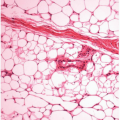

![]() Figure 6.3. Fungal infection. This erosion has acute inflammatory cells in the superficial epithelium, where fungal organisms were identified. |